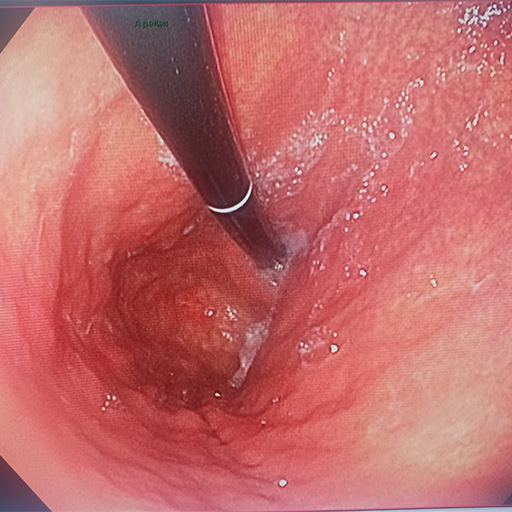

Gastroscopie

Examen de l'œsophage, de l'estomac et du début du duodénum

Coloscopie

Examen du colon, du rectum et de la partie terminale de l'intestin grêle